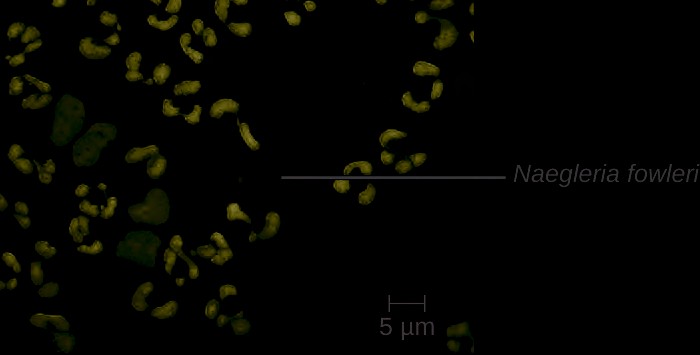

Hansen’s disease (also known as leprosy) is caused by a long, thin, filamentous rod-shaped bacterium Mycobacterium leprae, an obligate intracellular pathogen. M. leprae is classified as gram-positive bacteria, but it is best visualized microscopically with an acid-fast stain and is generally referred to as an acid-fast bacterium. Hansen’s disease affects the PNS, leading to permanent damage and loss of appendages or other body parts.

In the human body, M. leprae grows best at the cooler temperatures found in peripheral tissues like the nose, toes, fingers, and ears. Some of the virulence factors that contribute to M. leprae’s pathogenicity are located on the capsule and cell wall of the bacterium. These virulence factors enable it to bind to and invade Schwann cells, resulting in progressive demyelination that gradually destroys neurons of the PNS. The loss of neuronal function leads to hypoesthesia (numbness) in infected lesions. M. leprae is readily phagocytized by macrophages but is able to survive within macrophages in part by neutralizing reactive oxygen species produced in the oxidative burst of the phagolysosome. Like L. monocytogenes, M. leprae also can move directly between macrophages to avoid clearance by immune factors.

The extent of the disease is related to the immune response of the patient. Initial symptoms may not appear for as long as 2 to 5 years after infection. These often begin with small, blanched, numb areas of the skin. In most individuals, these will resolve spontaneously, but some cases may progress to a more serious form of the disease. Tuberculoid (paucibacillary) Hansen’s disease is marked by the presence of relatively few (three or less) flat, blanched skin lesions with small nodules at the edges and few bacteria present in the lesion. Although these lesions can persist for years or decades, the bacteria are held in check by an effective immune response including cell-mediated cytotoxicity. Individuals who are unable to contain the infection may later develop lepromatous (multibacillary) Hansen’s disease. This is a progressive form of the disease characterized by nodules filled with acid-fast bacilli and macrophages. Impaired function of infected Schwann cells leads to peripheral nerve damage, resulting in sensory loss that leads to ulcers, deformities, and fractures. Damage to the ulnar nerve (in the wrist) by M. leprae is one of the most common causes of crippling of the hand. In some cases, chronic tissue damage can ultimately lead to loss of fingers or toes. When mucosal tissues are also involved, disfiguring lesions of the nose and face can also occur ( Figure 26.11).

Hansen’s disease is diagnosed on the basis of clinical signs and symptoms of the disease, and confirmed by the presence of acid-fast bacilli on skin smears or in skin biopsy specimens (Figure 26.11). M. leprae does not grow in vitro on any known laboratory media, but it can be identified by culturing in vivo in the footpads of laboratory mice or armadillos. Where needed, PCR and genotyping of M. leprae DNA in infected human tissue may be performed for diagnosis and epidemiology.